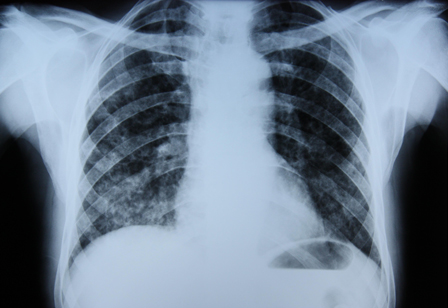

Radiografía de tórax que muestra una tuberculosis pulmonar con cavitación

De la colección personal del Dr. M. Narita, Departamento de Medicina Intensiva y Pulmonar, University of Washington